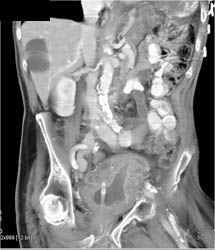

Cystocele